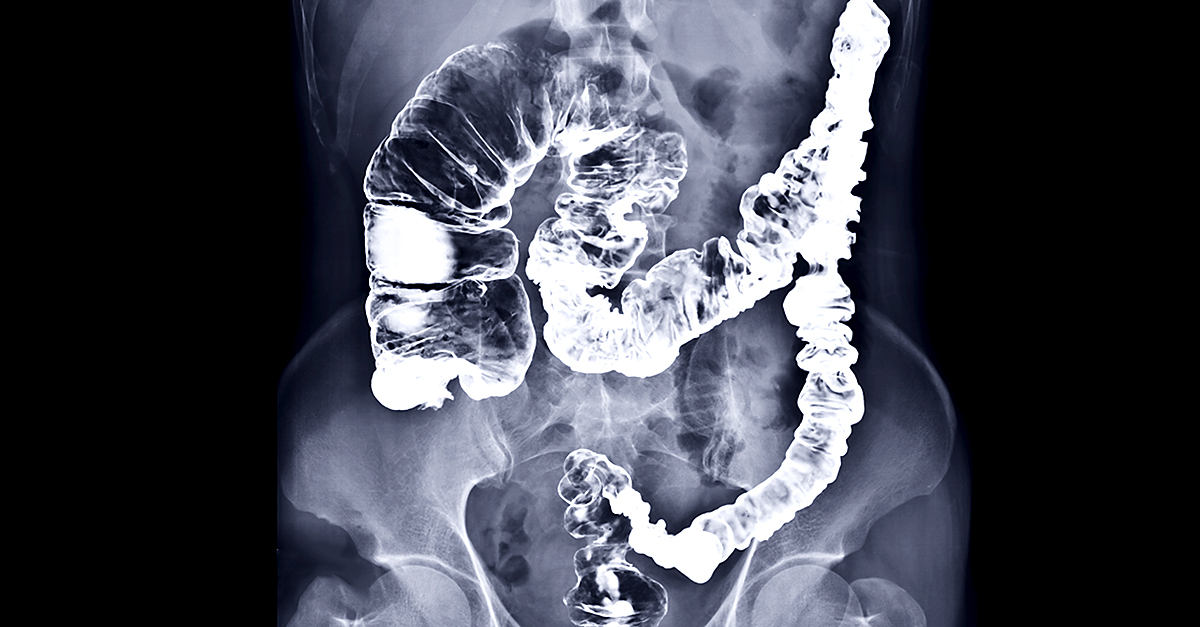

When discussing cancer screenings and images of the inside of the body, most people think of radiation. Actually, a variety of screening modalities are available for colorectal cancer and not all of them involve radiation exposure, Wong noted.

The next typical resource for colorectal cancer screening involves direct visualization.

"Only one of the direct visualization screening tests involves a CT scan, which would involve some potential radiation," Wong said. "When I say 'direct visualization,' you're basically using a scope or a long tube to look at the surface of the colon and see if you see any lesions."

He said other than the test involving a CT scan, none of the direct visualization options involve exposure to radiation.

When suspicious materials are detected or other red flags arise from a stool screening, a follow-up direct visualization is required to know how to best move forward, Wong explained, adding that a colonoscopy is probably the most common follow-up in these cases.

A colonoscopy can include the removal of potentially dangerous polyps, which can lead to bleeding or other potential complications. But the associated risks are heavily mitigated because a colonoscopy and other direct visualization procedures are conducted in a hospital or healthcare setting under the supervision of trained professionals.